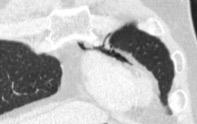

Raro. (2-9% de los T. tímicos). Asintomático. Contiene grasa (hasta 90%) y tejido timico (10-33%). Pueden ser muy grandes y confundirse con cardiomegalia. La tomografía “clásica” muestra los límites de la silueta cardiaca. (flechas)